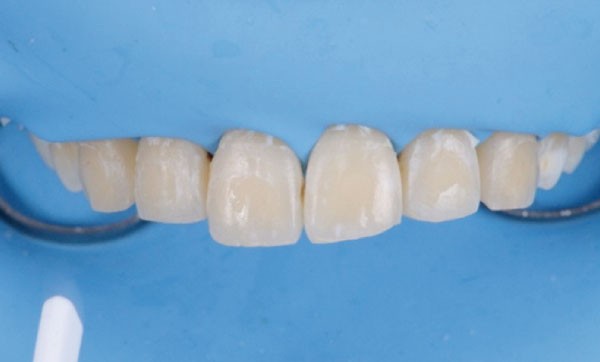

Bien que les dispositifs multi-attaches constituent actuellement une entrave à l’hygiène bucco-dentaire beaucoup moins importante que par le passé, ils demeurent en cas de défaillance de celle-ci un facteur d’apparition de lésions iatrogènes de l’émail appelées lésions opaques blanches ou leucomes.

Ce sont des hypominéralisations postéruptives de l’émail caractérisées par un élargissement des porosités amélaires. La structure cristalline est amoindrie mais présente. C’est un véritable échafaudage qui persiste malgré un stade plus ou moins avancé de dissolution minérale. Les leucomes sont décelables à l’œil nu si le corps de la lésion présente un déficit minéral de 10 % par rapport à l’émail sain. Ce déficit peut atteindre les 40 % à un stade avancé [1].

Il s’agit de l’effet iatrogène le plus fréquent des appareils orthodontiques fixes [2]. Selon les études, sa fréquence est comprise entre 2 et 97 % [2-5] et les lésions peuvent apparaître dès la 4e semaine de traitement [3]. Elles touchent le tiers cervical ou médian des faces vestibulaires des dents, autour des boîtiers orthodontiques. Les dents les plus concernées par ce type de lésion sont les incisives latérales maxillaires, suivies par les canines maxillaires, puis les canines mandibulaires. Les secteurs maxillaires sont 2,5 fois plus atteints que les secteurs mandibulaires [6].